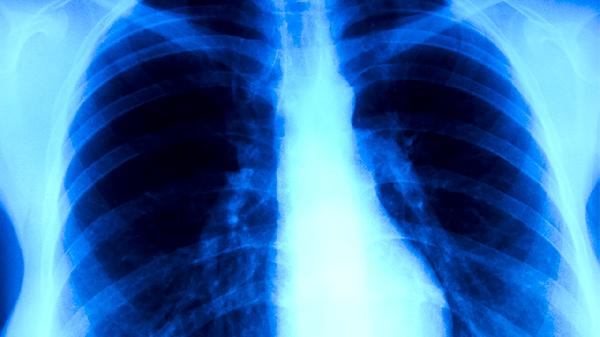

肺结核患者每日应保证1500-2000毫升饮水量,促进药物代谢和毒素排出。饮食需均衡摄入优质蛋白如鸡蛋、鱼肉,配合全谷物和新鲜蔬菜。避免辛辣刺激、油腻食物,戒烟戒酒。保持规律作息,居住环境注意通风换气,遵医嘱完成6-9个月规范治疗,定期复查胸部影像学和痰菌检测。